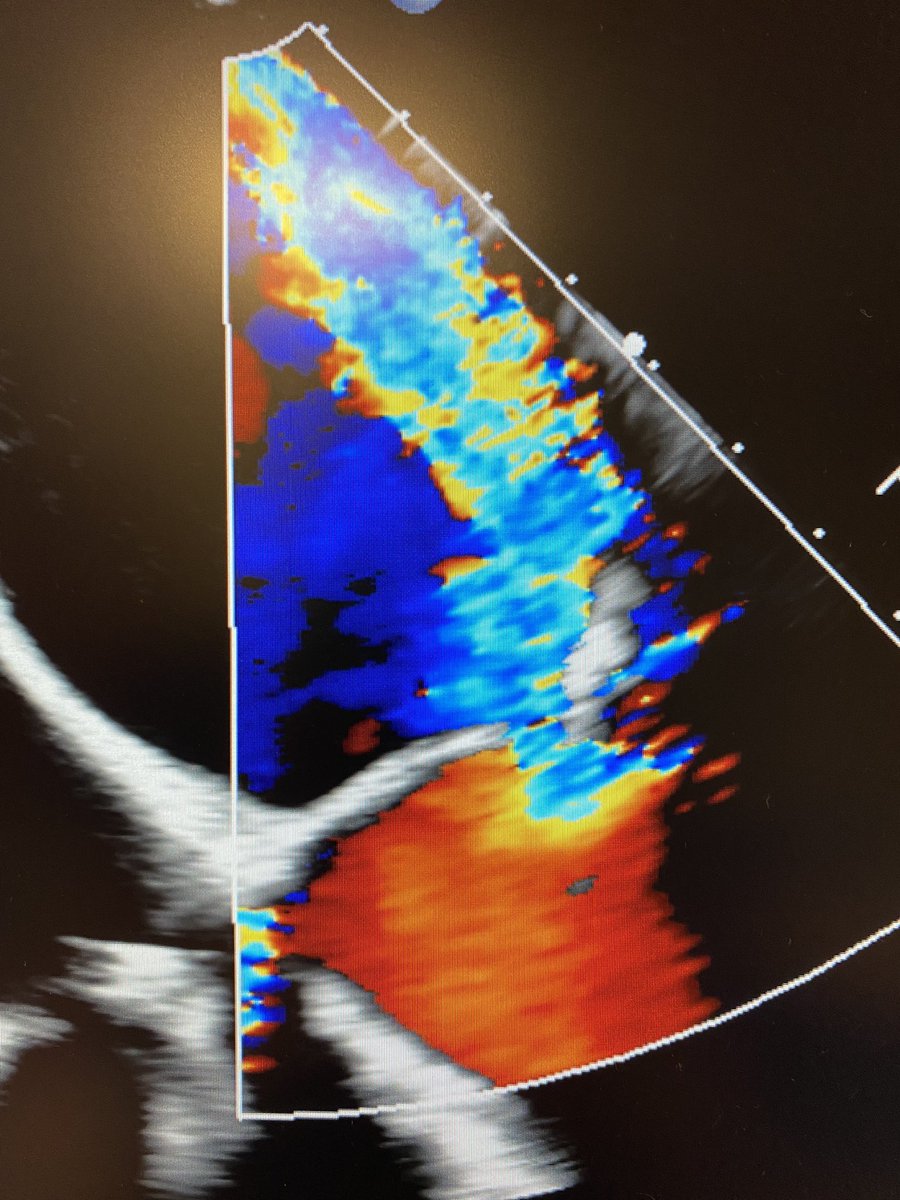

Just started using the brand new @ASE360 EchoGuide app - see images for assessment of an EROA in the MV with the PISA method. Works seamlessly and is so well designed! Congrats to all involved in creating this amazing tool for learners and all other echo aficionados !

Seattle, WA 🇺🇸 English